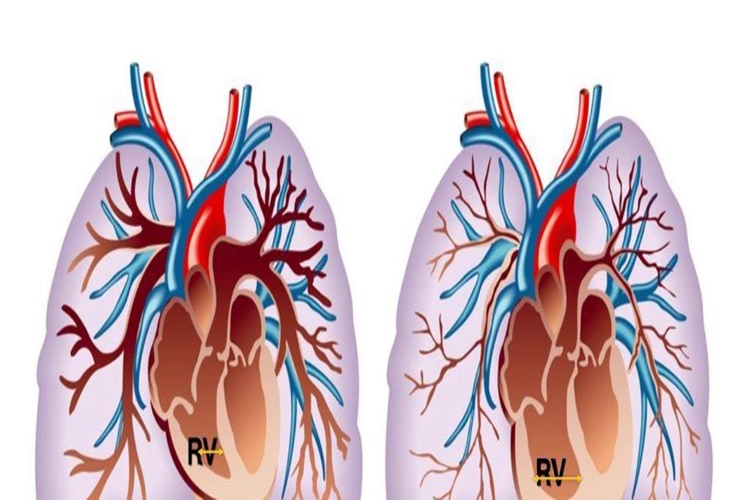

Akciğerde Şişlik Neden Olur?

Akciğerde şişlik, çeşitli sağlık sorunlarına bağlı olarak ortaya çıkabilir. İşte akciğerde şişliğe neden olabilecek bazı olası sebepler:

2. Akciğer Ödemi: Akciğer ödemi,

akciğer dokularının sıvı ile dolması durumudur. Kalp yetmezliği, akciğer

ödeminin yaygın bir nedenidir. Bu durumda, kalp zayıf bir şekilde kan

pompaladığında, kan akciğer damarlarında birikerek sıvı sızmasına neden

olabilir.

3. Akciğer Embolisi: Akciğer

arterlerinin bir emboli tarafından tıkanması, akciğer dokularında şişliğe neden

olabilir. Emboli genellikle bacak damarlarında oluşan pıhtıların akciğere

hareket etmesi sonucu ortaya çıkabilir.

Akciğerde şişlik belirtileri arasında nefes darlığı, öksürük, balgam, göğüs ağrısı, halsizlik gibi semptomlar yer alabilir.